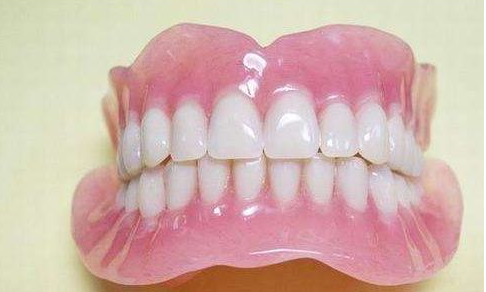

美观自然:吸附性义齿的外观与真牙相似,能够极大改善患者的牙齿缺失情况,提升美观度。